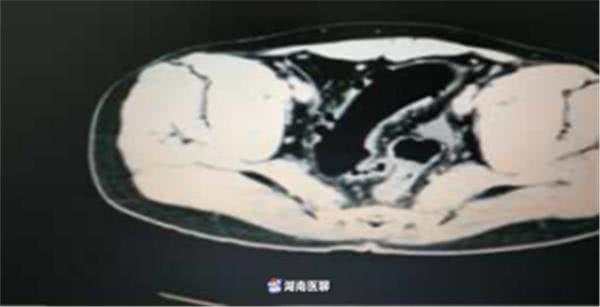

最近,衡陽市中心醫(yī)院胃腸外科接診了一位患者——巨大腸道異物。腹部CT提示:橫結(jié)腸末端-降結(jié)腸-乙狀結(jié)腸長條狀異常密度影,結(jié)合臨床病史,醫(yī)生考慮異物殘留可能。

(檢查結(jié)果)